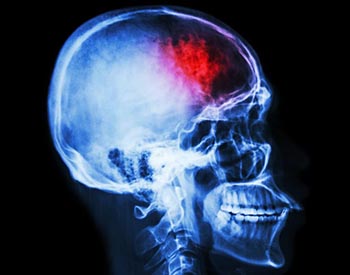

Se produce un derrame cerebral cuando el flujo sanguíneo no llega adecuadamente al cerebro. Esto ocurre cuando un vaso sanguíneo se rompe o se bloquea, impidiendo que el oxígeno de la sangre llegue a las células del cerebro. Dependiendo del tipo de derrame que se padezca el médico prescribirá uno u otro tratamiento, atendiendo a las necesidades de cada paciente.

Un derrame cerebral se da cuando el flujo sanguíneo de una parte del cerebro se interrumpe debido a que un vaso sanguíneo se ha roto o bloqueado, lo que impide la óptima llegada de sangre. Cuando esto ocurre, las células del cerebro no reciben el oxígeno y los nutrientes necesarios y, por ende, pueden llegar a morir dañando profundamente el cerebro.

- Derrame cerebral hemorrágico. se trata de un accidente vascular que ocurre cuando un vaso sanguíneo cerebral se daña o se rompe, lo que provoca que la sangre se escape y se derrame por el cerebro, provocando una hemorragia intracraneal que suele dañar las membranas que rodean el órgano.